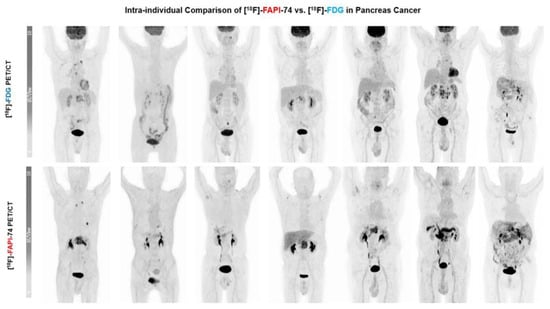

3.3. [18F]FAPI-74 Uptake in Tumor Lesions